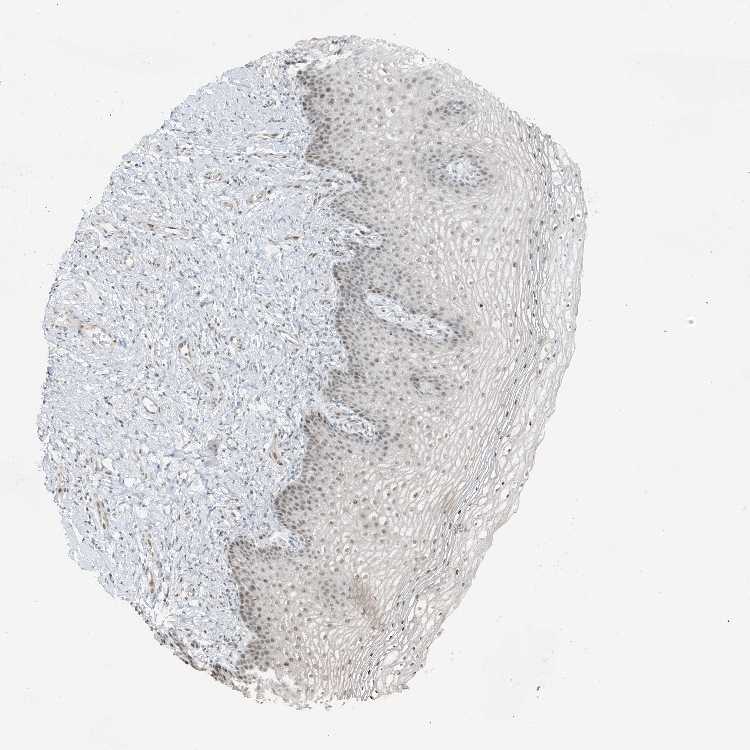

VAGINA - Antibody stainingi

Antibody staining in the annotated cell types in the current human tissue is reported as not detected, low, medium, or high, based on conventional immunohistochemistry profiling in selected tissues. This score is based on the combination of the staining intensity and fraction of stained cells.

Each image is clickable and will lead to virtual microscopy that enables deeper exploration of all samples and also displays staining intensity scores, fraction scores and subcellular localization as well as patient and tissue information for each sample.

Antibody HPA035498

Squamous epithelial cells Medium